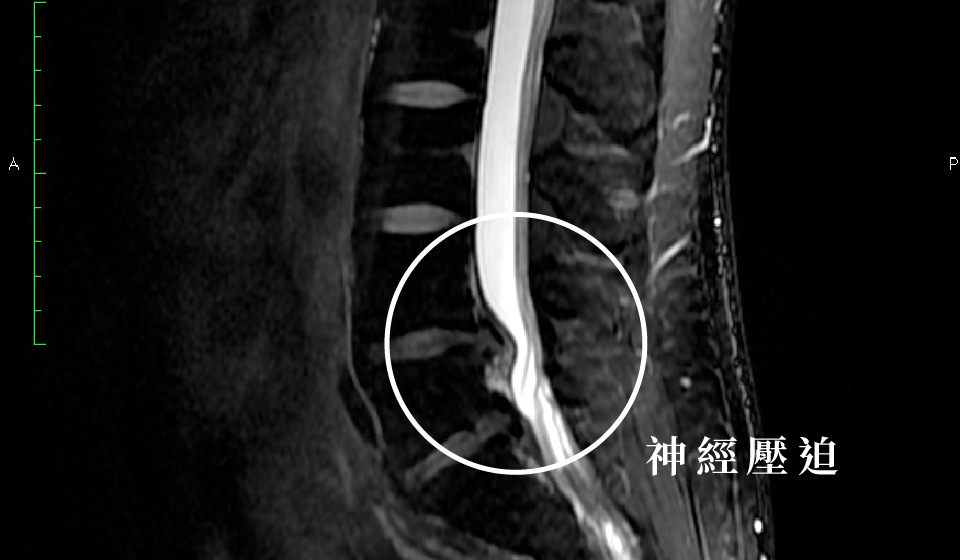

事後發現這並不能真正解決問題,後來的一段時間,Kun哥除了腰部、下背疼痛外,左腿更是出現發麻的情形,於是連續到幾間大醫院進行檢查,幾乎每位醫師都建議要開刀,因為Kun哥的腰椎第四節椎間盤不僅裂開,斷裂部分還明顯滑脫,嚴重壓迫到腰椎神經。